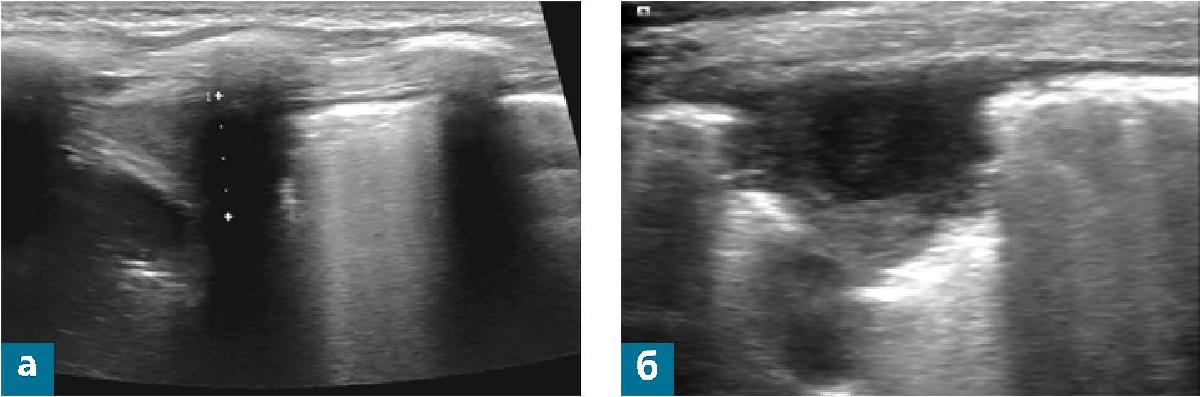

- В нижнебоковых отделах легкого определяются множественные широкие и сливные В-линии, консолидация толщиной до 16 мм, с обедненной воздушной бронхограммой и кровотоком при ЦДК (рис. 2 а).

- Структура консолидации неоднородная.

- В составе определяется отграниченная полость диаметром до 10 мм с утолщенными до 1,2 мм стенками, с неоднородным жидкостным содержимым за счет гиперэхогенных линейных включений (рис. 2 б, в).

- При цветовом доплеровском картировании (ЦДК) сосудистый рисунок в компримированной части легочной ткани сохранен, в зоне «белого легкого» не прослеживается.

- В остальных участках с обеих сторон поверхностные отделы легких воздушны, достоверная эхографическая оценка глубже расположенных участков легочной ткани невозможна.

- От поверхности легких распространяется типичный реверберационный артефакт в виде А-ли-ний и единичные тонкие В-линии в количестве не более двух в срезе (за исключением базальных отделов, где линии наблюдаются в количестве до четырех в срезе).

- Регистрируется свободная жидкость в левой плевральной полости, выраженные интерстициальные изменения в базальных отделах левого легкого (рис. 2 г).

Заключение: эхо-признаки консолидации, абсцесса нижней доли левого легкого. Свободная жидкость в левой плевральной полости (рис. 2).

Рис. 2 (а - г). Полипозиционное УЗ-исследование органов грудной клетки мальчика Б. на четвертый день болезни.